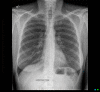

Contraceptive implant migration into the pulmonary circulation is an uncommon, but potentially serious complication. We describe an "aspiration" technique for percutaneous retrieval of a contraceptive implant from a subsegmental pulmonary artery, using a Penumbra Neuron MAX 088 guiding catheter and a Merit Medical VacLok Vacuum Pressure Syringe, as an alternative to the previously described snare technique. Our patient had an uneventful recovery and was discharged home on the same day.